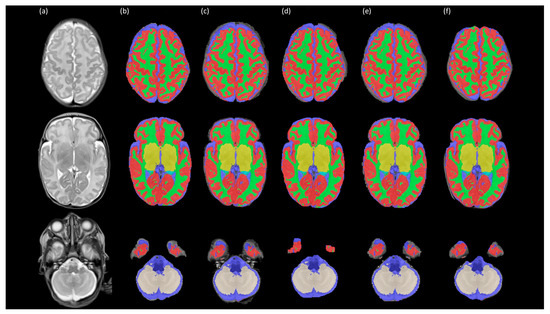

3.1. Assessment of Intensity Variability and Segmentation Performance

3.2. Assessment of Regional Brain Volume Measurements After Different Preprocessing Steps

3.2.1. Comparison Between Bias Field Correction Methods

3.2.2. Comparison Amongst Brain Extraction Methods